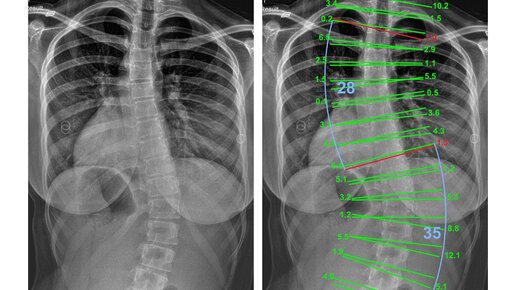

Существует несколько классификаций степеней сколиоза. Но, по большому счету, степени не важны. Просто при I степени требуется только наблюдение, а при IV – встает вопрос об операции. Что же тогда важно? Важны градусы искривления. В Сколиолоджик.ру используют модифицированную методику Кобба. В свое время врач Джон Роберт Кобб, американский хирург-ортопед, предложил следующую систему измерения угла искривления. Он провел линии, одна из которых параллельна верхней границе тела верхнего позвонка, а...